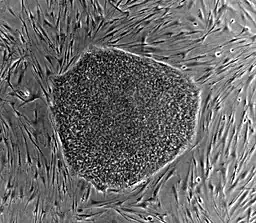

Human embryonic stem cells

A: Stem cell colonies that are not yet differentiated.

B: Nerve cells, an example of a cell type after differentiation.